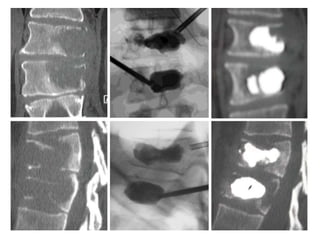

It is importantto fill the anterior 2/3–3/4 of the vertebral body

Cement should reachor cross the midline to reinforce both halves of the vertebra (white arrows)

A Unipedicular PV showsdistribution of cement into both halves of the vertebra

Inflatable ballon inthe midline of the fractured body Tip of the guide pin over the center of the vertebral body